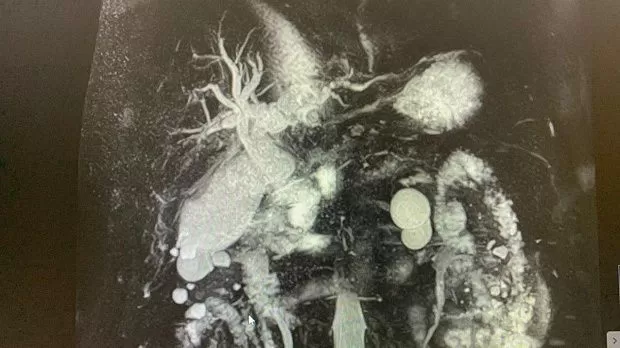

2)Биохимический анализ крови: Билирубин- 82,4 , прямой- 47,5 АЛТ- 92 , АСТ-136 , С-реактивный белок -44,4 скорость клубочковой фильтрации- 45 . МРТ: внутри- и внепеченочные протоки расширены , общий печеночный проток до 18 мм, холедох до 14 мм, в просвете конкременты до 14 мм. Заключение: Холедохолитиаз . Билиарная гипертензия.